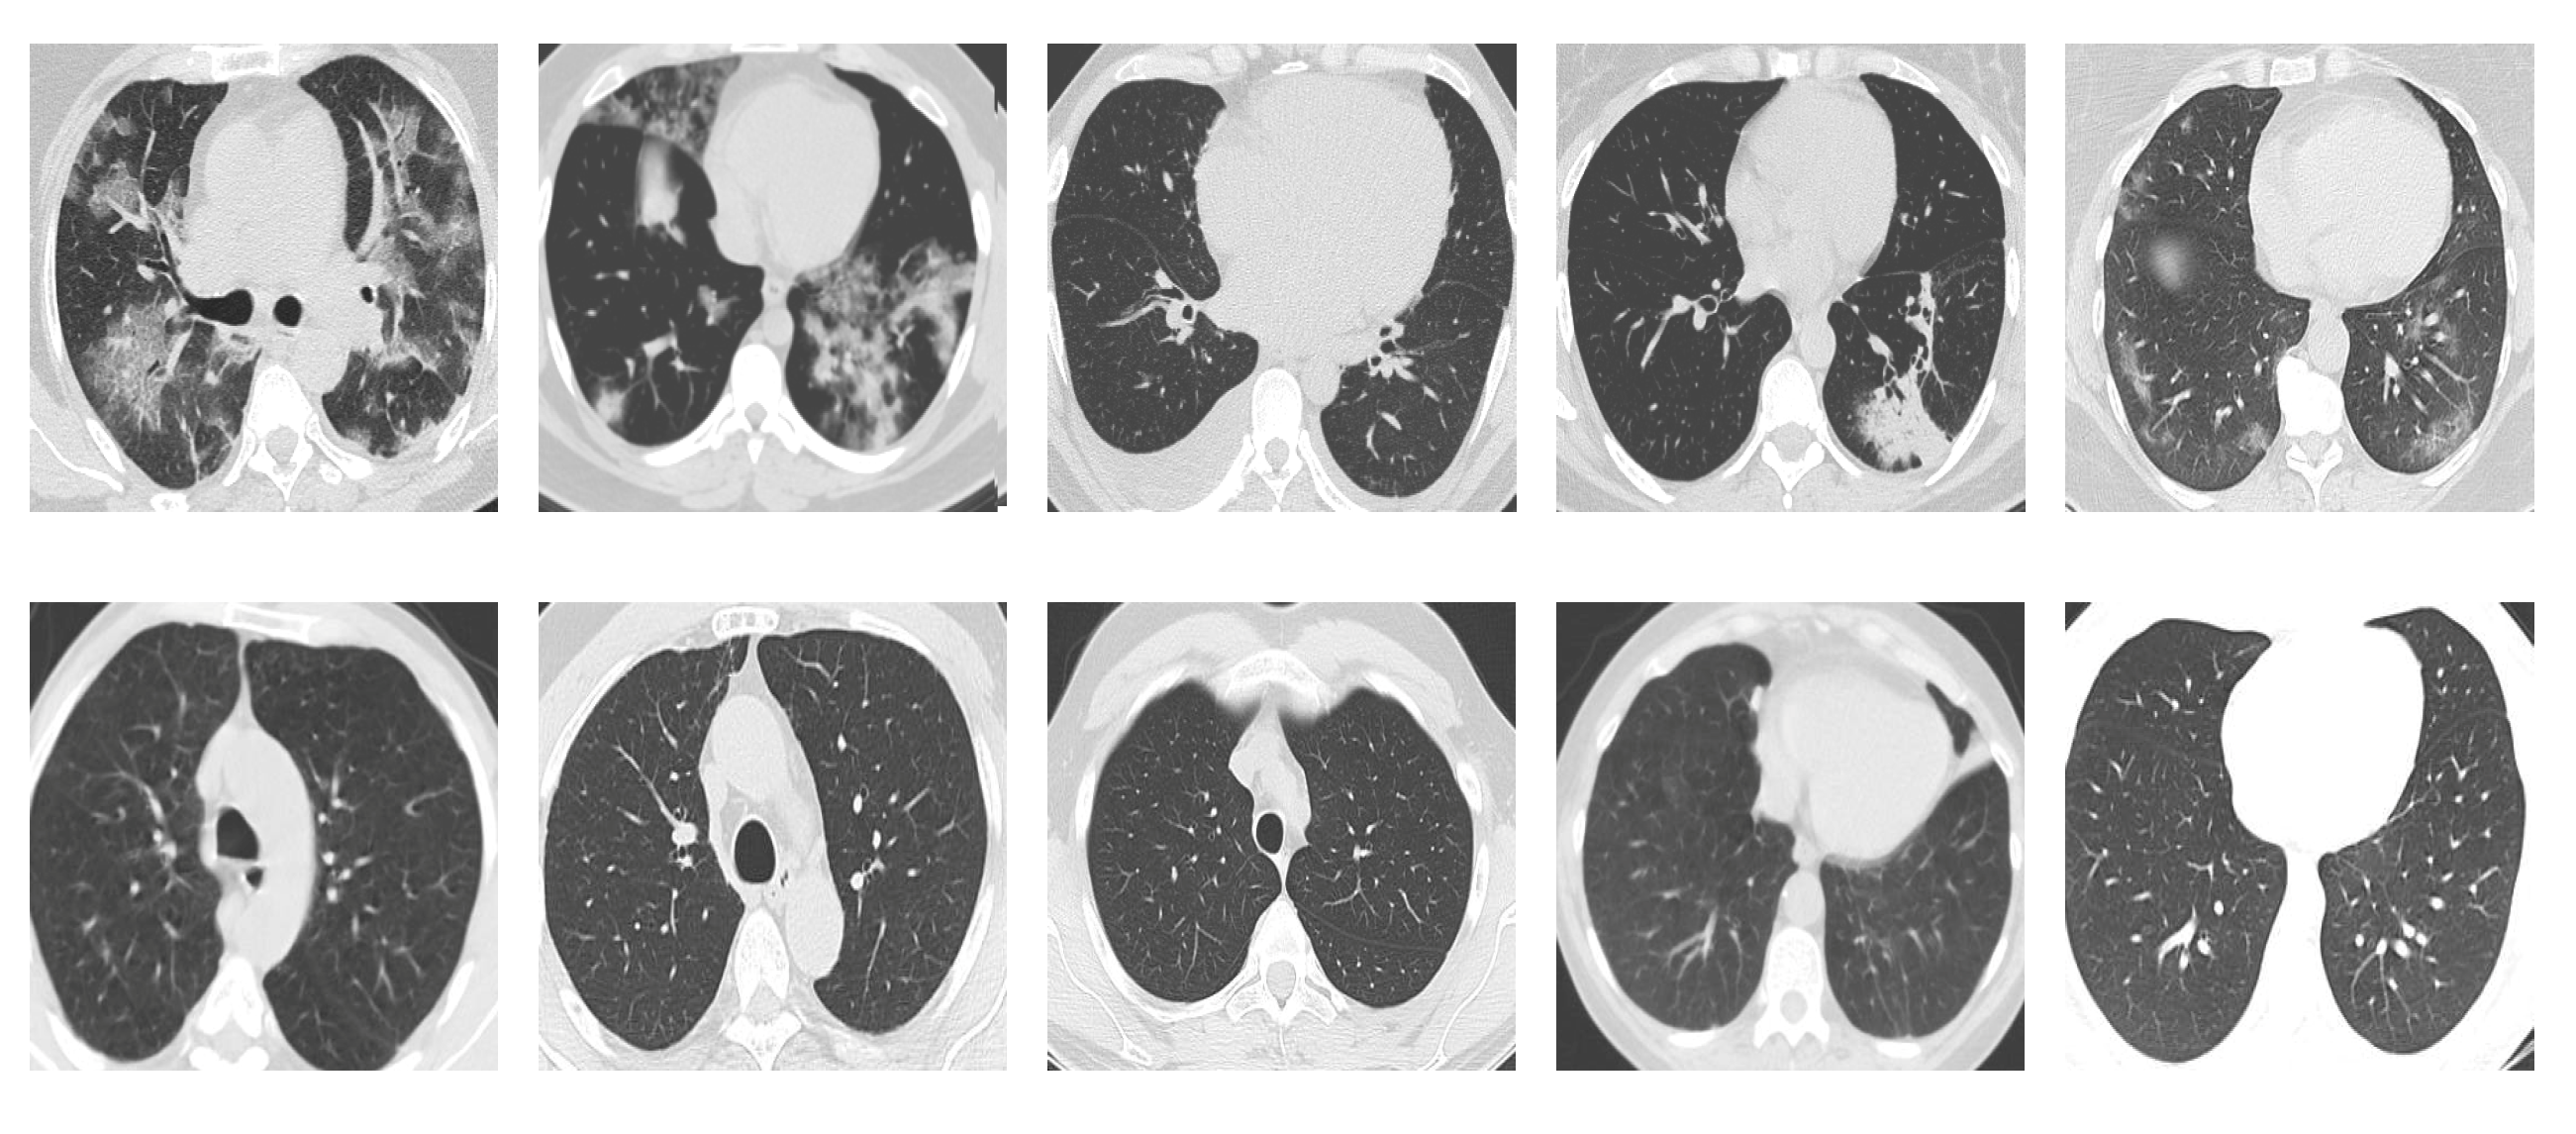

SARS-CoV-2 CT Scan dataset [53]: The dataset was collected from hospitals of Sao Paulo, Brazil, with a total of 2482 CT scans acquired from 120 patients of both genders. It is composed of 1252 scans for patients infected with SARS-CoV-2, and 1230 scans for patients infected with other lung diseases. The CT scans have varying spatial sizes between and , and are available in PNG format. CT scans from this dataset are shown in Figure 7.

Figure 7.

Examples of chest CT scans from the SARS-CoV-2 CT dataset. The first row represents CT scans diagnosed with COVID-19, whereas the second row represents non-COVID-19.